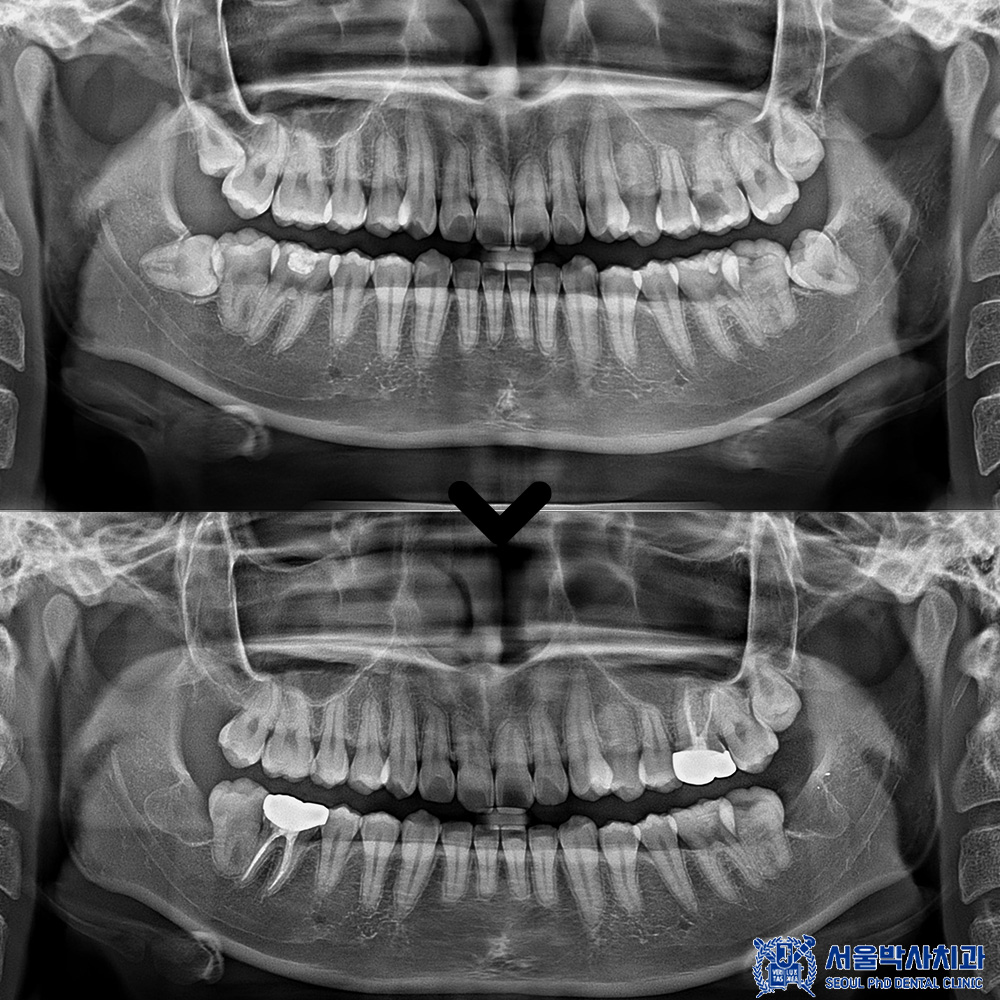

자세히 확인을 해보기 위해

파노라마를 촬영해 보았습니다.

파노라마 상에서도

다수 우식이 발견되었습니다.

신흥동치과 서울박사는

자연치아를 살리는 방향으로 진단하고

또 꼭 필요한 진료만 권해드리고자

충치가 깊지 않은 곳은 레진이나 인레이로,

충치가 깊은 곳은 신경치료 및 크라운으로

자연치아 보존 방향으로 치료를 계획하였습니다.